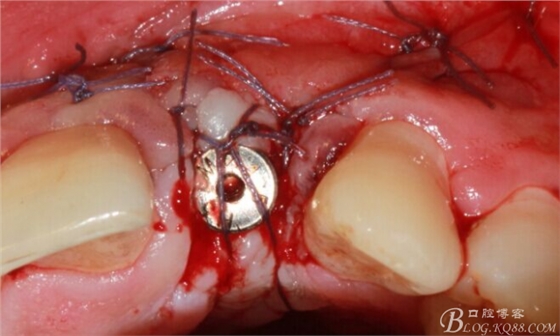

于是我果斷告知患者,手術(shù)失敗了,不能拖延,如不及時(shí)處理,炎癥繼續(xù)發(fā)展會(huì)很快波及鄰牙牙槽骨。患者接受我的建議。切開翻瓣,骨粉及生物膜消失了,骨吸收嚴(yán)重,幸運(yùn)的是,因?yàn)樘幚砑皶r(shí),鄰牙骨支持依然存在。

徹底掻刮。